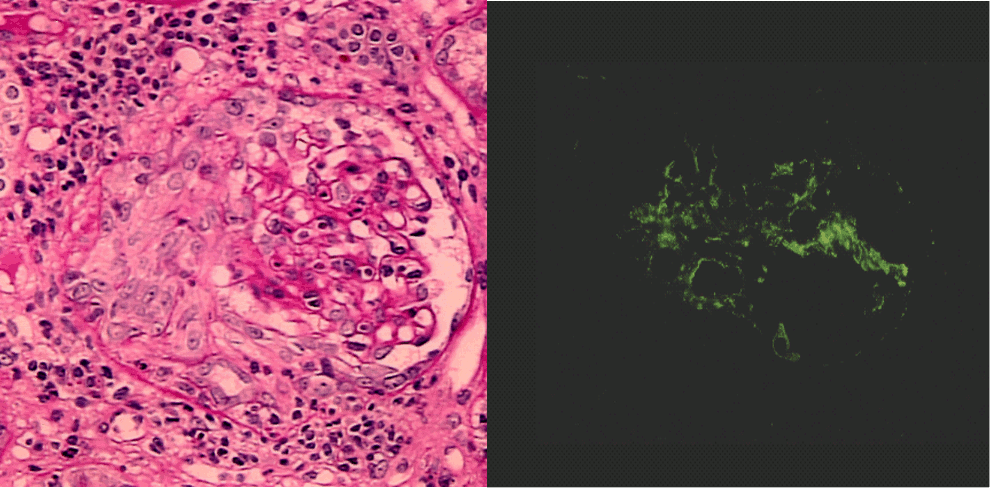

- 막성 신장병증: 신증후군 또는 신염 증후군의 양상을 보일 수 있다. 약 2/3는 인지질 A2 수용체에 대한 자가항체와 관련이 있지만, 폐암, 대장암, B형 간염, 말라리아, 페니실라민, 전신성 홍반성 루푸스 등과도 관련될 수 있다. 뇌실 단락술을 받은 사람은 단락 신염이 발생할 위험이 있으며, 이는 종종 막성 신장병증을 유발한다. 현미경 관찰 결과, 사구체 세포 과다 증식 없이 사구체 기저막이 비후되는 특징을 보인다. 면역형광 검사에서 IgG의 광범위한 과립상 흡수가 나타나며, 기저막이 과립 침착물을 완전히 둘러싸 "스파이크 앤 돔" 패턴을 형성한다. 세뇨관은 III형 과민 반응의 증상을 보이며, 내피 세포 증식으로 PAS 염색에서 관찰 가능하다. 예후는 1/3은 무기한 지속, 1/3은 관해, 1/3은 말기 신부전으로 진행된다. 질병 진행 시 코르티코스테로이드로 치료를 시도한다. 극히 드물게 가족성으로 유전되는 경우도 있다.

- 제1형: 굿파스처 증후군으로, 폐에도 영향을 미치는 자가면역 질환이다. 사구체 기저막에 대한 IgG 항체가 염증 반응을 유발하여 신염 증후군과 혈액 기침을 유발한다.[4] 고용량 면역 억제 요법(정맥 내 메틸프레드니솔론)과 시클로포스파미드, 혈장 교환술이 필요하다. 면역 조직 화학 염색은 선형 IgG 침착을 보여준다.

괴사반월체성 사구체신염은 신장 생검의 형광 항체법 소견에 따라 다음과 같이 분류된다.[11]

- 선상형 (항사구체 기저막 항체형 신염 등)

- 과립형 (전신 홍반 루푸스나 IgA 혈관염 등)

- 미량 면역 (pauci-immune) 형 (ANCA 관련 신염 등)